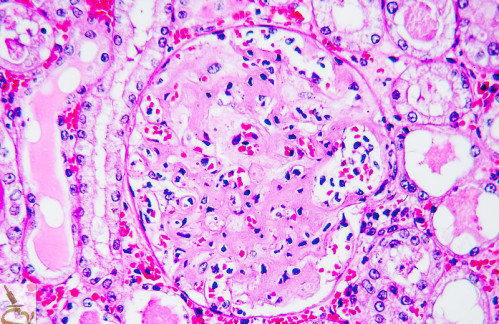

Jornadas sobre AMILOIDOSIS: lo que necesitas saber